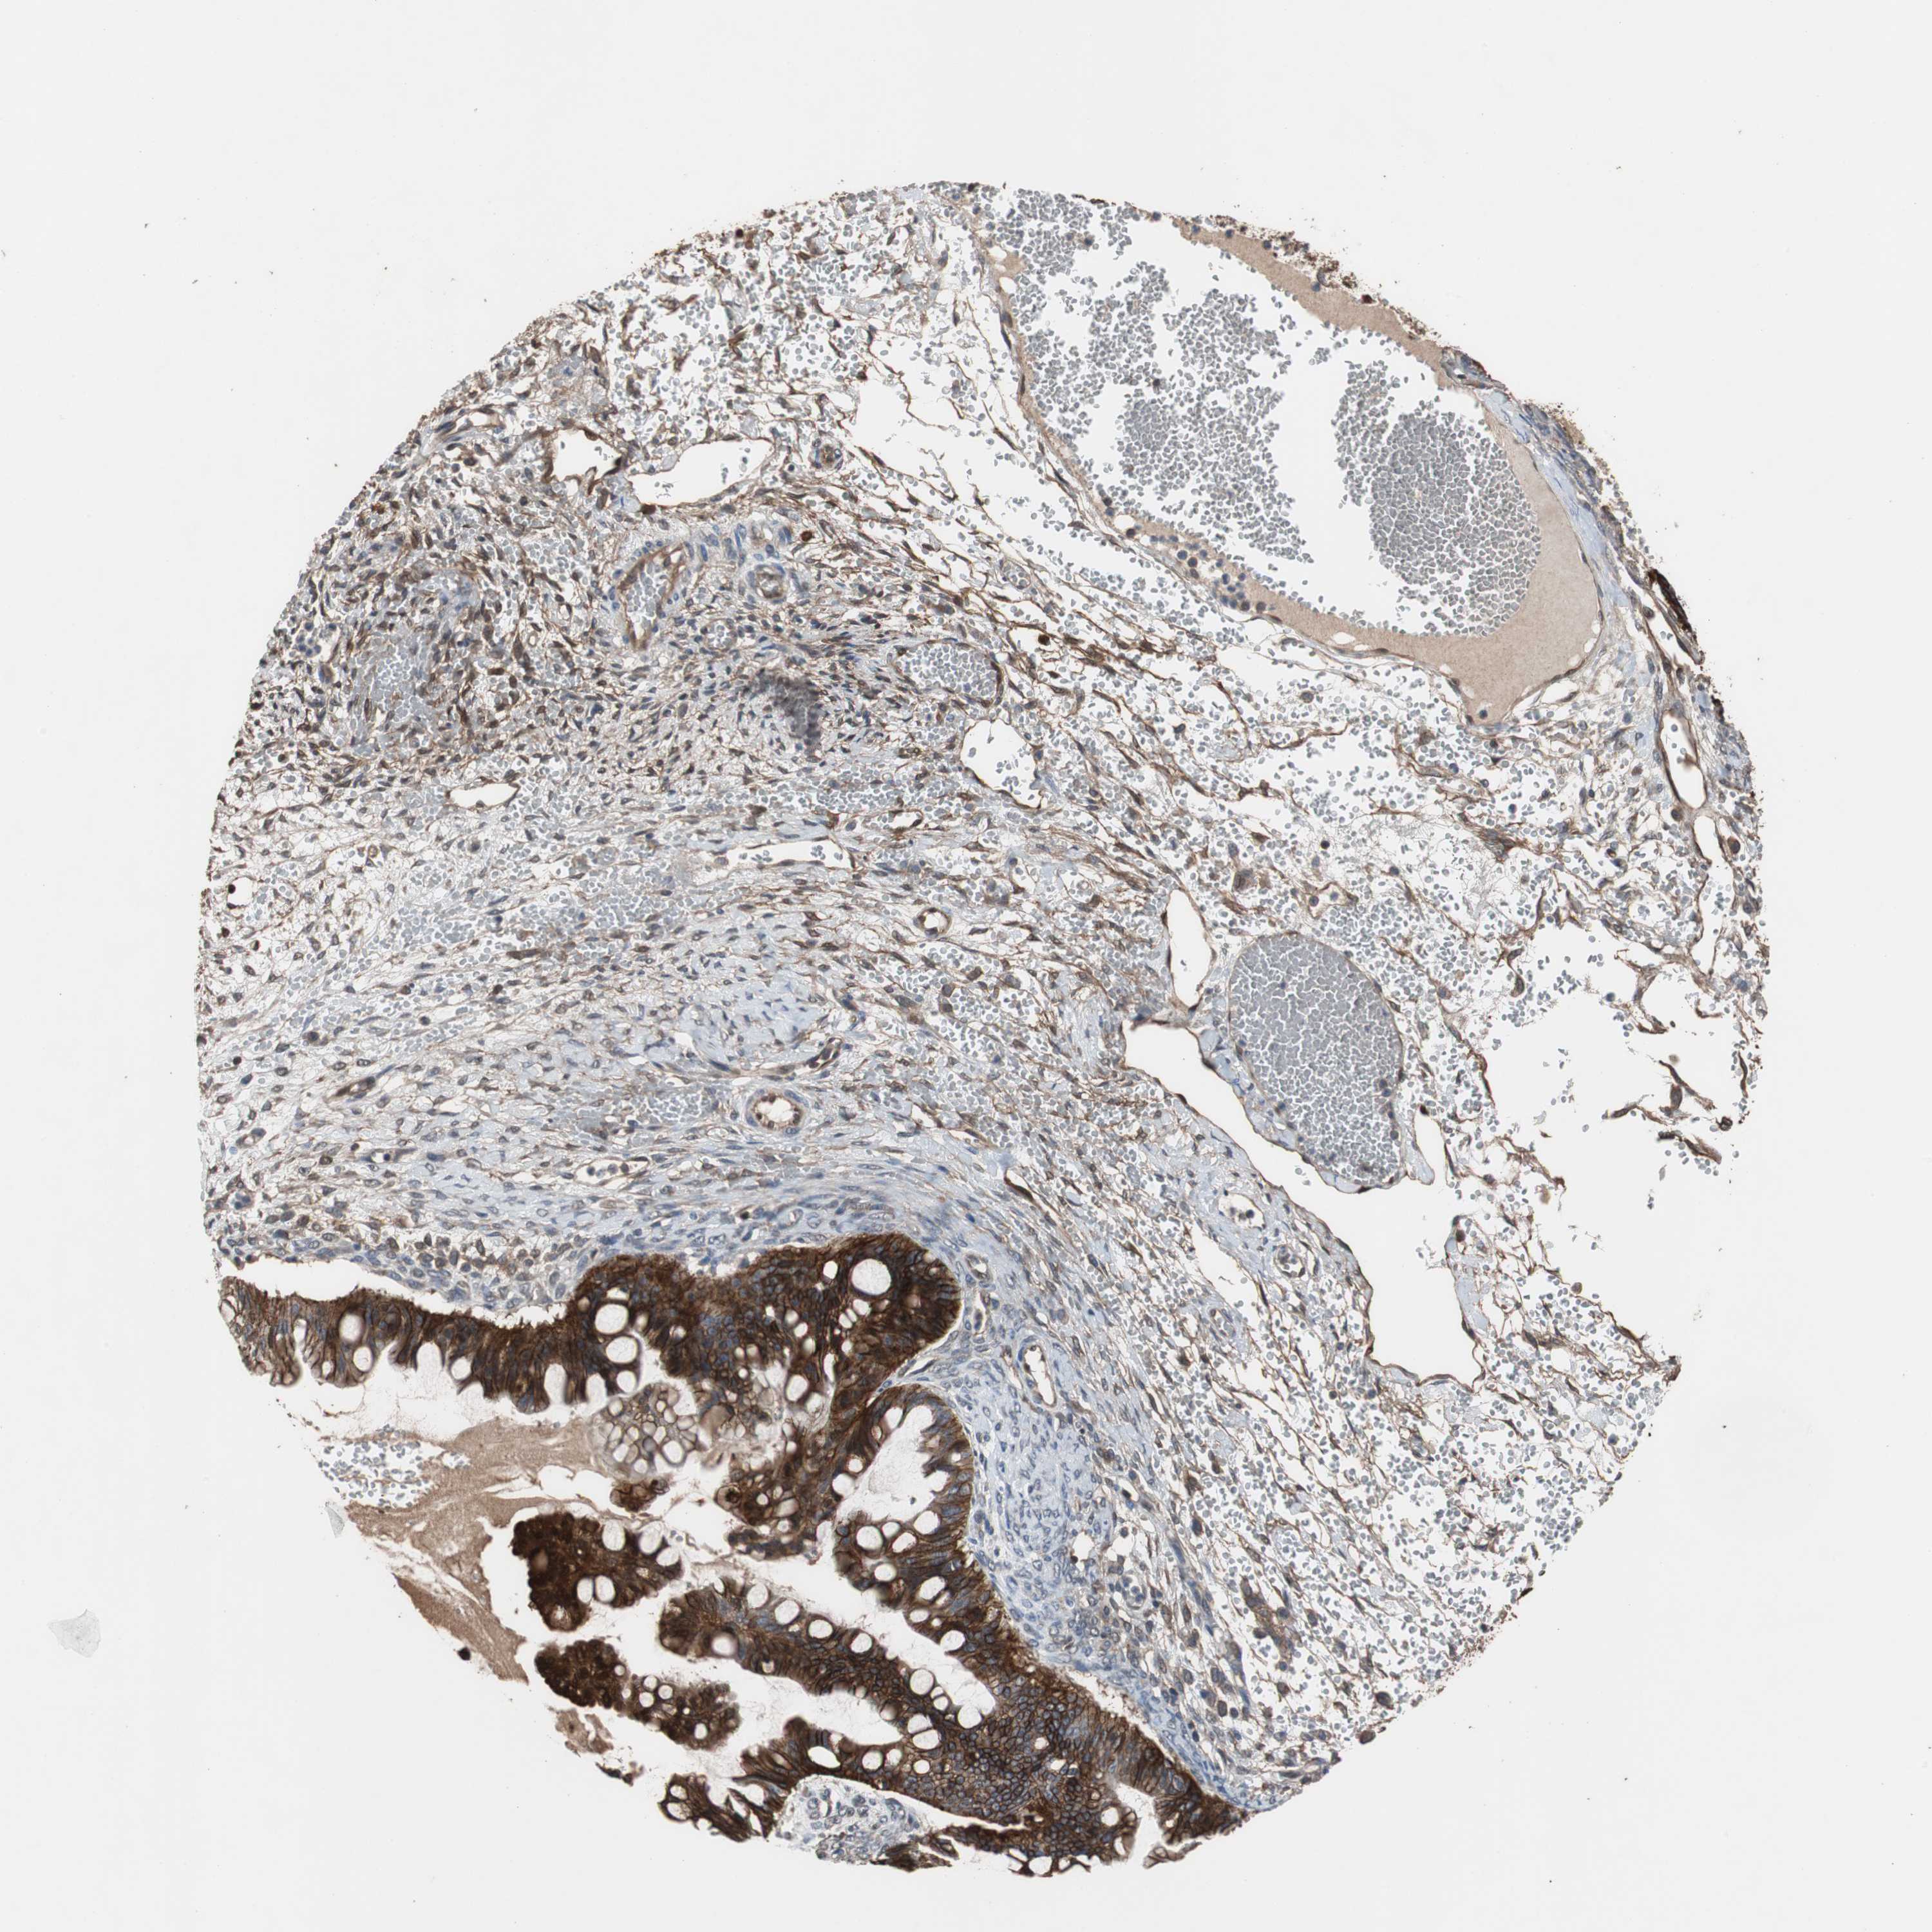

OVARIAN CANCER - Protein expressioni

A mouse-over function shows sample information and annotation data. Click on an image to view it in a full screen mode. Samples can be filtered based on level of antibody staining by selecting one or several of the following categories: high, medium, low and not detected. The assay and annotation is described here.

Note that samples used for immunohistochemistry by the Human Protein Atlas do not correspond to samples in the TCGA dataset.

Antibody stainingi

Antibody staining in the annotated cell types in the current human tissue is reported as not detected, low, medium, or high, based on conventional immunohistochemistry profiling in selected tissues. This score is based on the combination of the staining intensity and fraction of stained cells.

Each image is clickable and will lead to virtual microscopy that enables deeper exploration of all samples and also displays staining intensity scores, fraction scores and subcellular localization as well as patient and tissue information for each sample.

Antibody HPA006881

Staining

High

Medium

Low

Not detected

Intensity

Strong

Moderate

Weak

Negative

Quantity

>75%

75%-25%

<25%

None

Location

Nuclear

Cytoplasmic/membranous

Cytoplasmic/membranous,nuclear

Cystadenocarcinoma, serous, NOS

Cystadenocarcinoma, mucinous, NOS

Carcinoma, endometroid